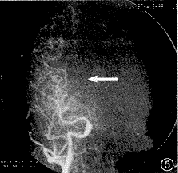

患者女,28岁。因突然发生左眼视3天,于1998年8月2日入院。入院后3天亦发生右眼视。发病初期患者曾有一过性头痛,双眼左侧视物障碍,检查视力双眼均为1.2,无昏迷、呕吐,无肢体和面部的偏瘫及知觉丧失,无语言障碍。体检未见异常。眼部检查:右眼视力1.2,左眼1.5。双眼球运动正常,眼前节及屈光间质正常。散瞳检查眼底:双眼视乳头边界清晰,视网膜无出血、渗出,视网膜动静脉比例正常,黄斑区无水肿,中心窝反光存在。辅助检查:头部CT扫描及增强扫描未见异常;TBC微机中心视野计检查及周边弓形视野计检查,示双眼左侧一致性偏盲,有黄斑回避。于同年8月27日由颅脑外科经右侧腹股沟穿刺行全脑血管造影术(图1~6)。诊断:右大脑后动脉阻塞;右大脑前动脉先天性缺如。

图1 左椎动脉造影正位片,右大脑后动脉显影较左大脑后动脉弱,示末端有阻塞因素存在

图2 右椎动脉造影正位片,示右大脑后动脉显影较左大脑后动脉弱,示末端有阻塞因素存在